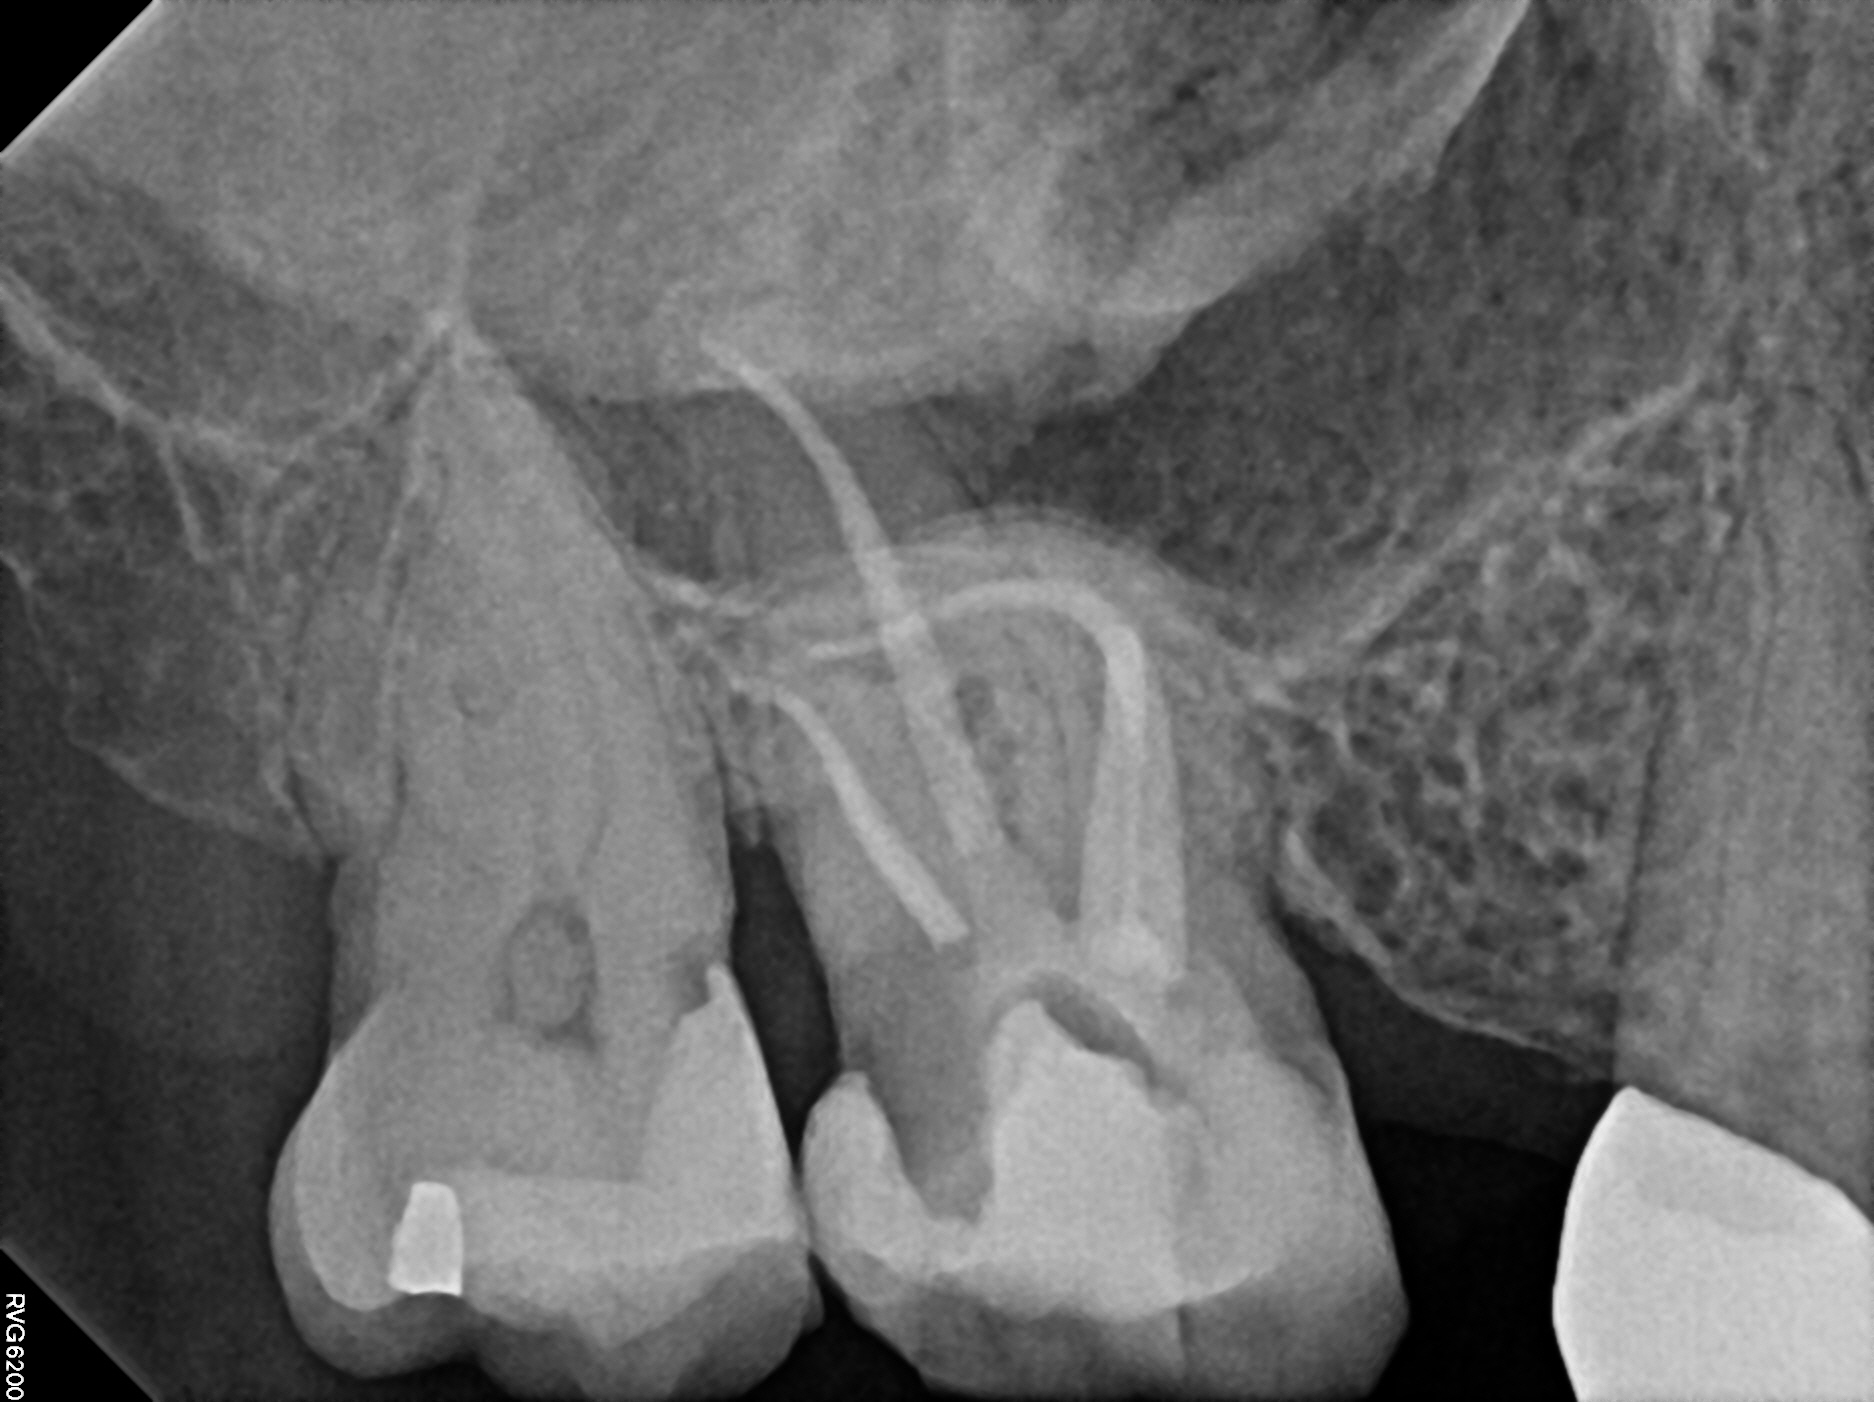

Case 2

This is a retreatment case. The picture on the left shows a lower molar that had been root canal treated many years prior, but either did not heal or at some point afterward became re-infected. The lesion is quite large, extending to the inferior alveolar nerve. While retreating the case Dr Cottle found a previously missed nerve canal (three in one root, five total in this one molar) and was able to disinfect all the canals again. The image on the right shows the completely healed bone one year later.